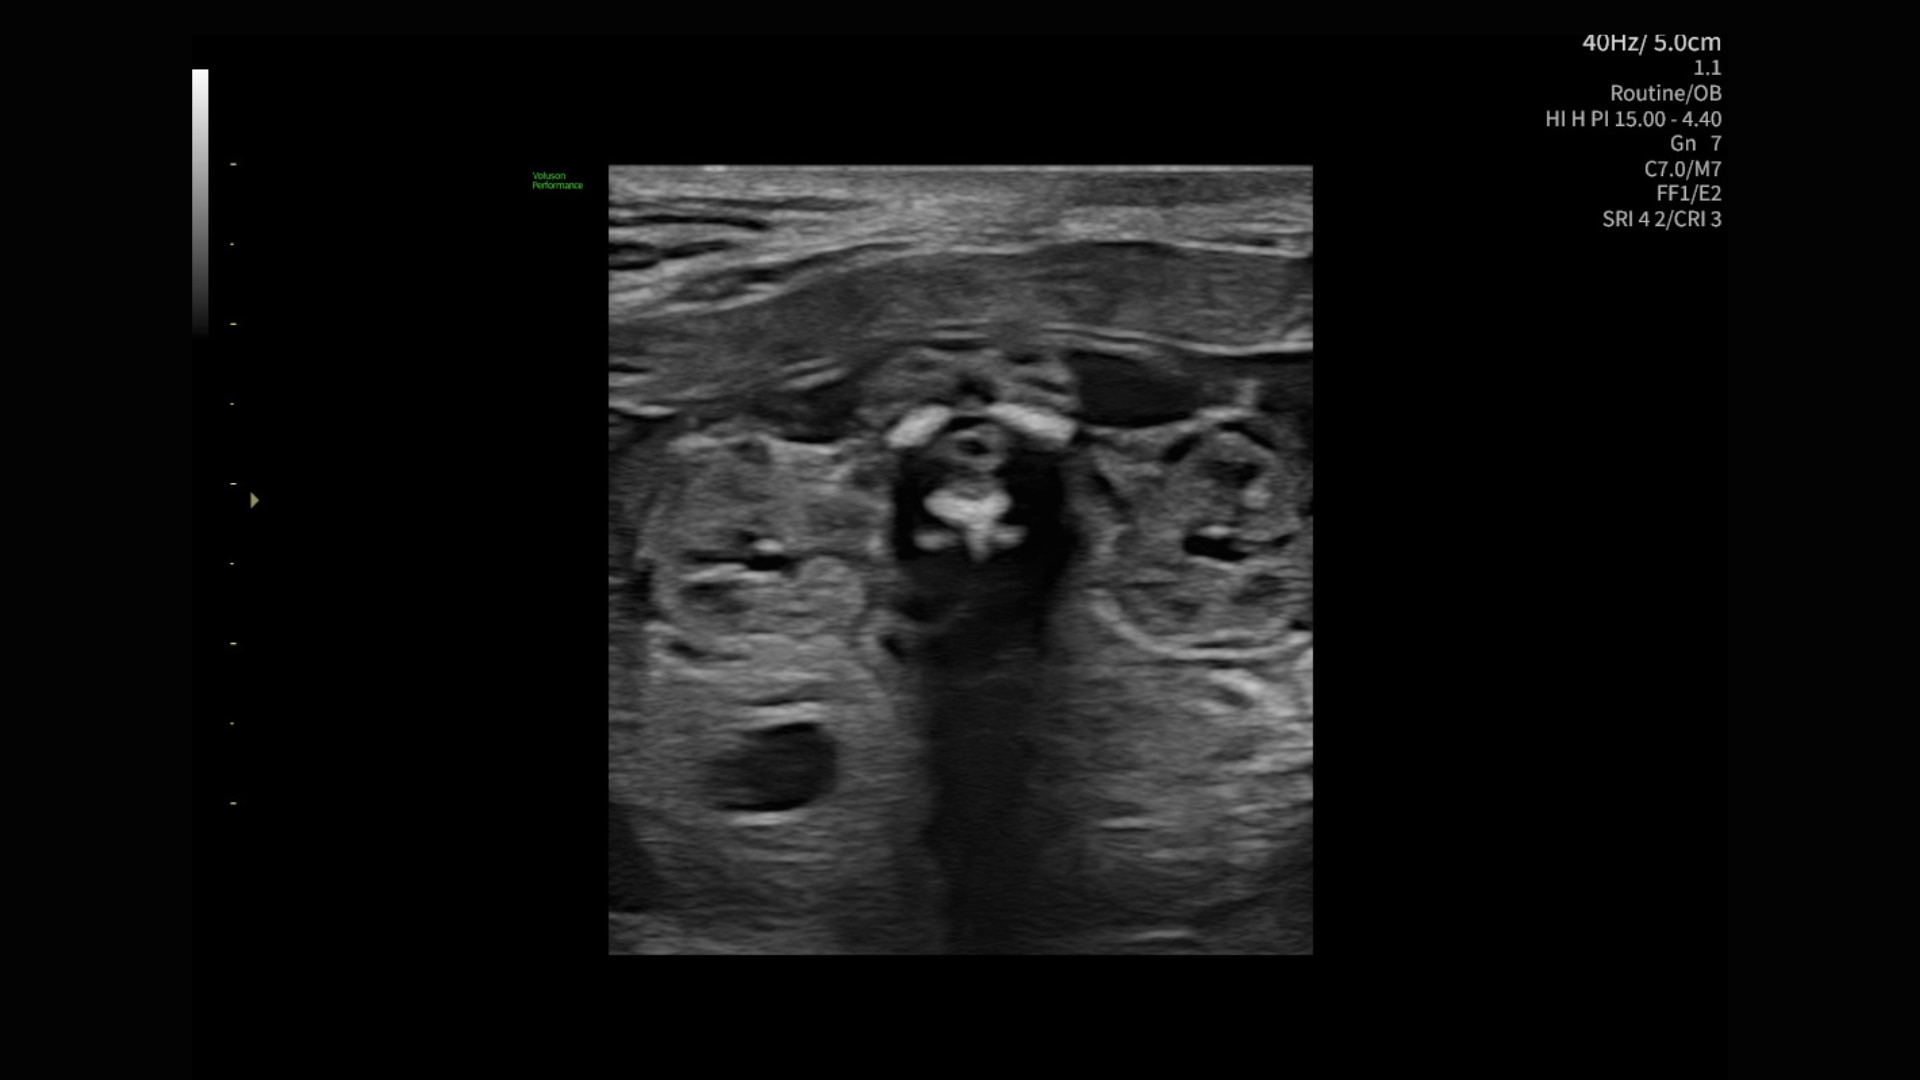

88%

Segment fibroids with 88% accuracy using Fibroid Mapping